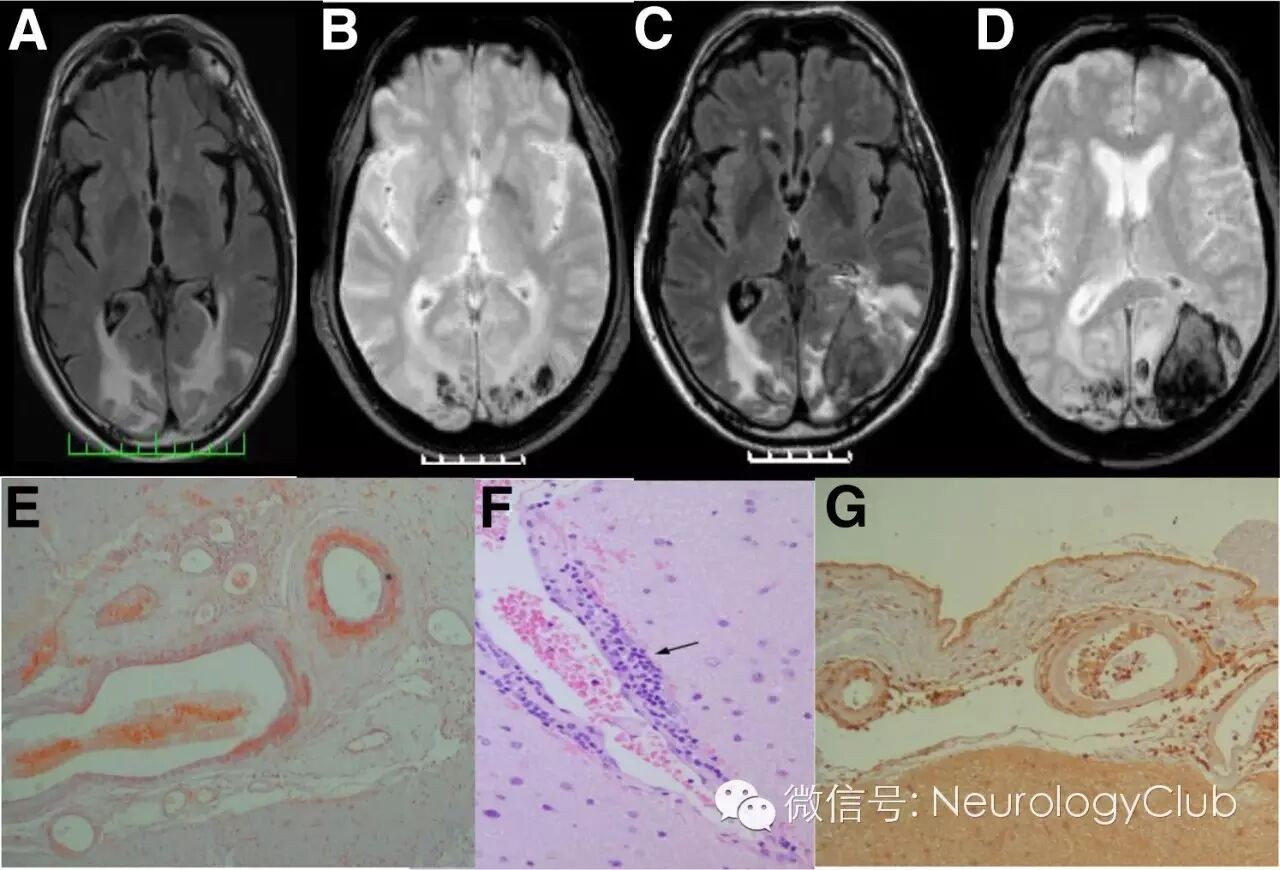

(A-B:FLAIR和T2*WI提示对称性后部颞枕区血管源性水肿伴出血和散在微出血;C-D:第二次入院时的FLAIR和T2*WI提示左侧颞枕区出血;E:柔脑膜和脑实质血管Aβ沉积[刚果红染色,×4];F-G:血管外周淋巴细胞炎性浸润[HE,×20;CD3染色,×10])

A-B:治疗前的FLAIR和T2*WI;C-D:免疫抑制治疗后FLAIR和T2*WI提示病灶明显减少;E-F:脑实质和柔脑膜血管壁淀粉样蛋白沉积[Aβ4染色,×10;刚果红染色,×10];G:柔脑膜血管周围淋巴细胞浸润[CD3染色,×10]